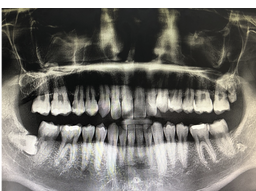

사랑니 발치 후 주의사항 알아봐요 사랑니 발치 후 주의사항에 대해 알아보려고 합니다. 사랑니는 대부분 어린 시절에 발생하는 치아로, 일반적으로 18~25세 사이에 생기는 3번째 대구치를 말합니다. 일반적으로는 상아질로 된 다른 이빨과 마찬가지로 식이기구의 일환으로 사용되지만, 때로는 주변 치아와 충돌하여 통증이나 발치가 필요한 경우도 있습니다.사랑니는 일반적으로 적절한 공간이 없어서 자리를 잡지 못하고 다른 이빨과 충돌할 가능성이 높습니다. 이러한 충돌은 주변 치아의 이상을 유발할 수 있으며, 치아의 교정이 필요할 수도 있습니다.

사랑니 발치는 일반적으로 부분 마취 후 수술실에서 이루어집니다. 수술 전에는 환자의 건강 상태와 치아의 위치와 상태를 파악하기 위해 치과 전문의가 진단을 하게 됩니다.